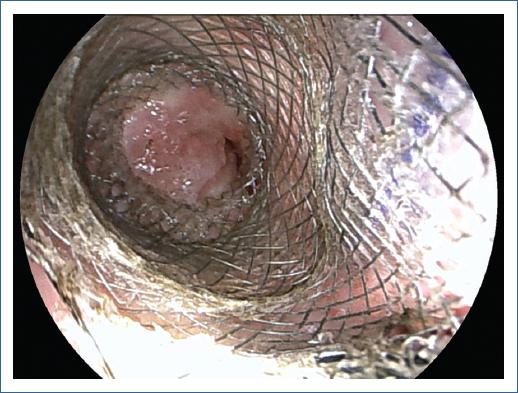

Se utilizó una LAMS (Hot Axios, Boston Scientific) de 15 mm de diámetro bajo visión endoscópica con ayuda de ecoendoscopio lineal (Fujifilm EG-580UT) con canal de trabajo 3.8 mm de la siguiente manera: se introdujo ecoendoscopio a hipofaringe y bajo visión endoscópica se avanzó guía biliar 0.035” (Jagwire, Boston Scientific) a través del orificio proximal del catéter de la LAMS verificando fluroscópicamente adecuado avance distal de la guía al ascenso colónico. Se realizó liberación de LAMS de 15 mm bajo visión endoscópica logrando adecuada paliación de la estenosis retirando ecoendoscopio. Se introdujo gastroscopio de 9.6 mm (Fujifilm EG-760R) dilatando la LAMS a 15 mm con balón hidrostático (CRE, Boston Scientific) permitiendo avance de gastroscopio apreciando mucosa colónica normal distal a la estenosis. La paciente cursó con dolor posprocedimiento el cual fue manejando con tramadol gotas (25 mg cada 6 horas) teniendo adecuada tolerancia a la dieta sólida. El LAMS fue retirado 6 semanas después sin eventualidades con adecuada remodelación de la anastomosis con paso libre del gastroscopio, tras lo cual fue retirado (Fig. 2). En el seguimiento a 8 semanas tras la retirada de la LAMS la paciente continua sin disfagia, siendo evaluada con el puntaje EAT-10, presentando un descenso de 17 puntos previo al procedimiento a 3 puntos luego de su retiro, con incremento de 6 kg y sin necesidad de nueva dilatación endoscópica.